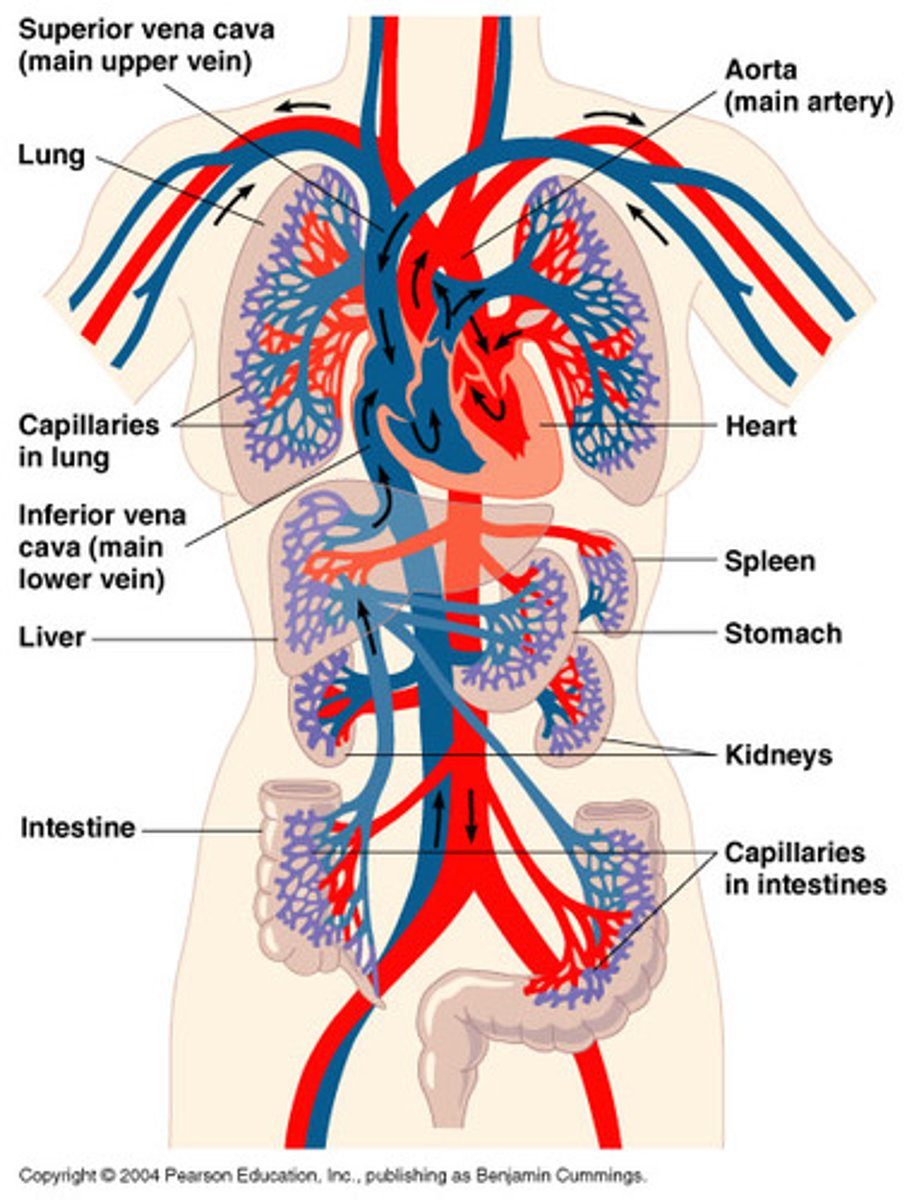

What is the cardiovascular system?

Includes heart and all blood vessels

Delivers oxygen, nutrients, hormones, and waste products throughout the body. Contributes to temperature regulation.